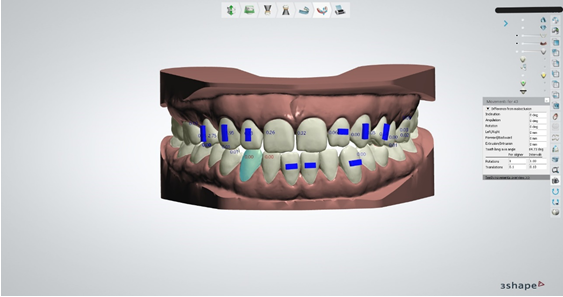

Slika1. Napomena je ta da bi svi ortodontski radovi koji se izvode u laboratoriju trebali biti odrađeni u suradnji sa specijalistom ortodoncije koji bi morali biti nositelji takvih radova ili kao nositelji radova ili kao posrednici između ordinacija I laboratorija.

Sl.1

Slika 9. Nakon svih odrađenih faza pristupamo zapravo najkraćoj fazi, a najbitnijoj, samoj prepostavi zuba koja u dizajnu vrlo sliči postavi zuba u mobilnoj protezi u fazi voska. Ono što je naš posao je dovesti zube u položaj koji je ortodont odredio u što je moguće precizniju poziciju poštujući iznose koje je ortodont odredio za pomake poput mezijalizacije, distalizacije, intruzije, ekstruzije, rotacije, angulacije, inklinacije itd. U to možemo biti sigurni jer nam za svaki pomak koji napravimo za pojedini zub sustav izbacuje sa strane iznose pomaka koje napravimo. Ako željena pozicija zuba prelazi vrijednosti koje je ortodont postavio onda je svakak potrebna dodatna konzultacija sa ortodontom da procjeni dali će ekscesivna vrijednost dovesti do neželjene recesije.